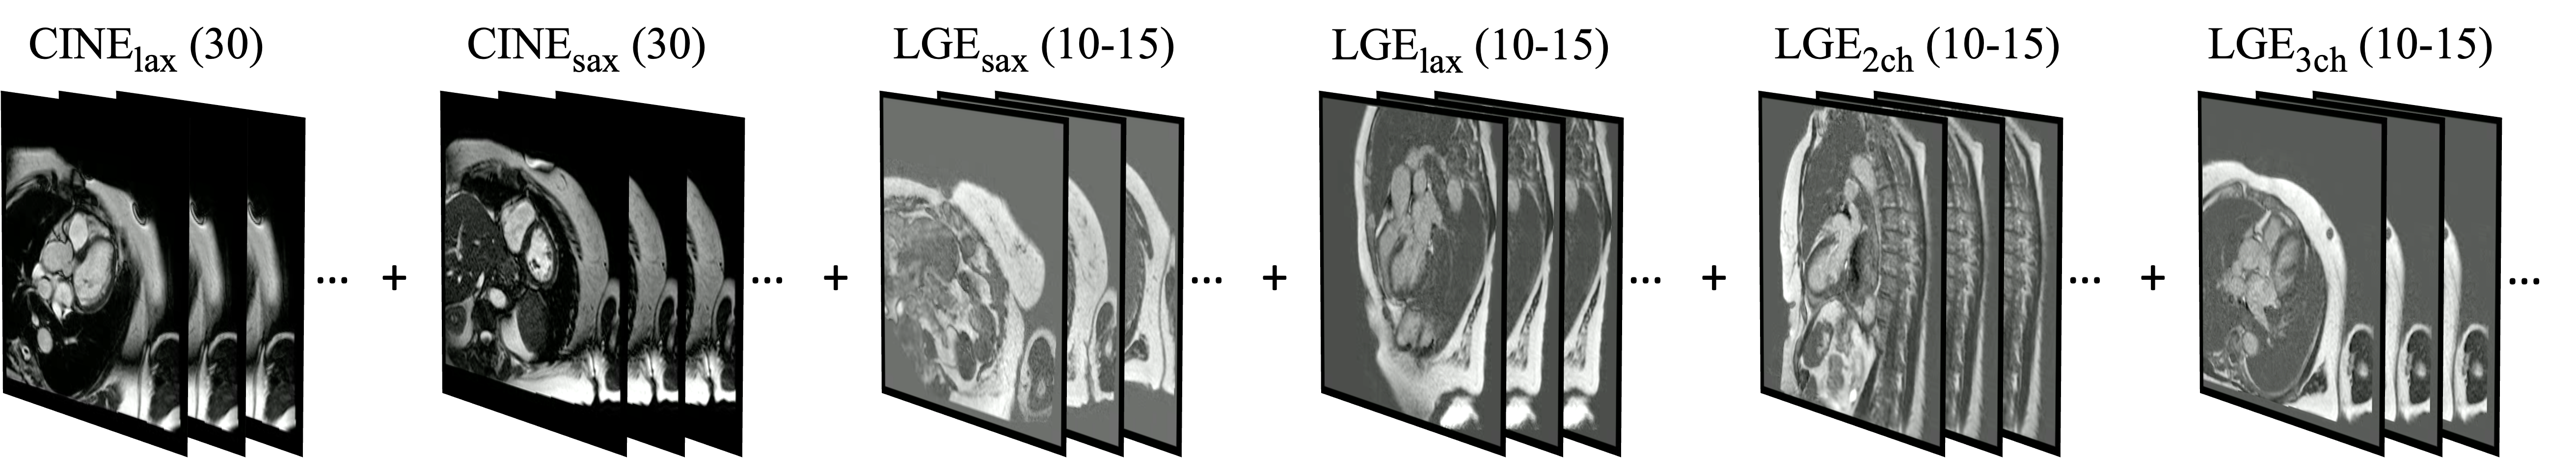

In this work, we define the different settings as IMAGE-TYPEview, where IMAGE-TYPE is the type of the image, and view𝑣𝑖𝑒𝑤{view} is the view of the image. Multiple views of the same image type are joined with “-”. For example, CINElax-sax refers to the long-axis and short-axis view of CINE. An example of video constructed using CINElax-sax + LGElax-sax-2ch-3ch is shown in Figure 4.

Refer to caption

Figure 4: Example of CMR image sequences constructed by CINElax-sax + LGElax-sax-2ch-3ch, where (\cdot) represents the number of images of each type-view combination. For CINElax-sax, each frame represents the time dimension. For LGEsax, each frame corresponds to the depth dimension, and for LGElax-2ch-3ch, each image is duplicated to be consistent with LGEsax.